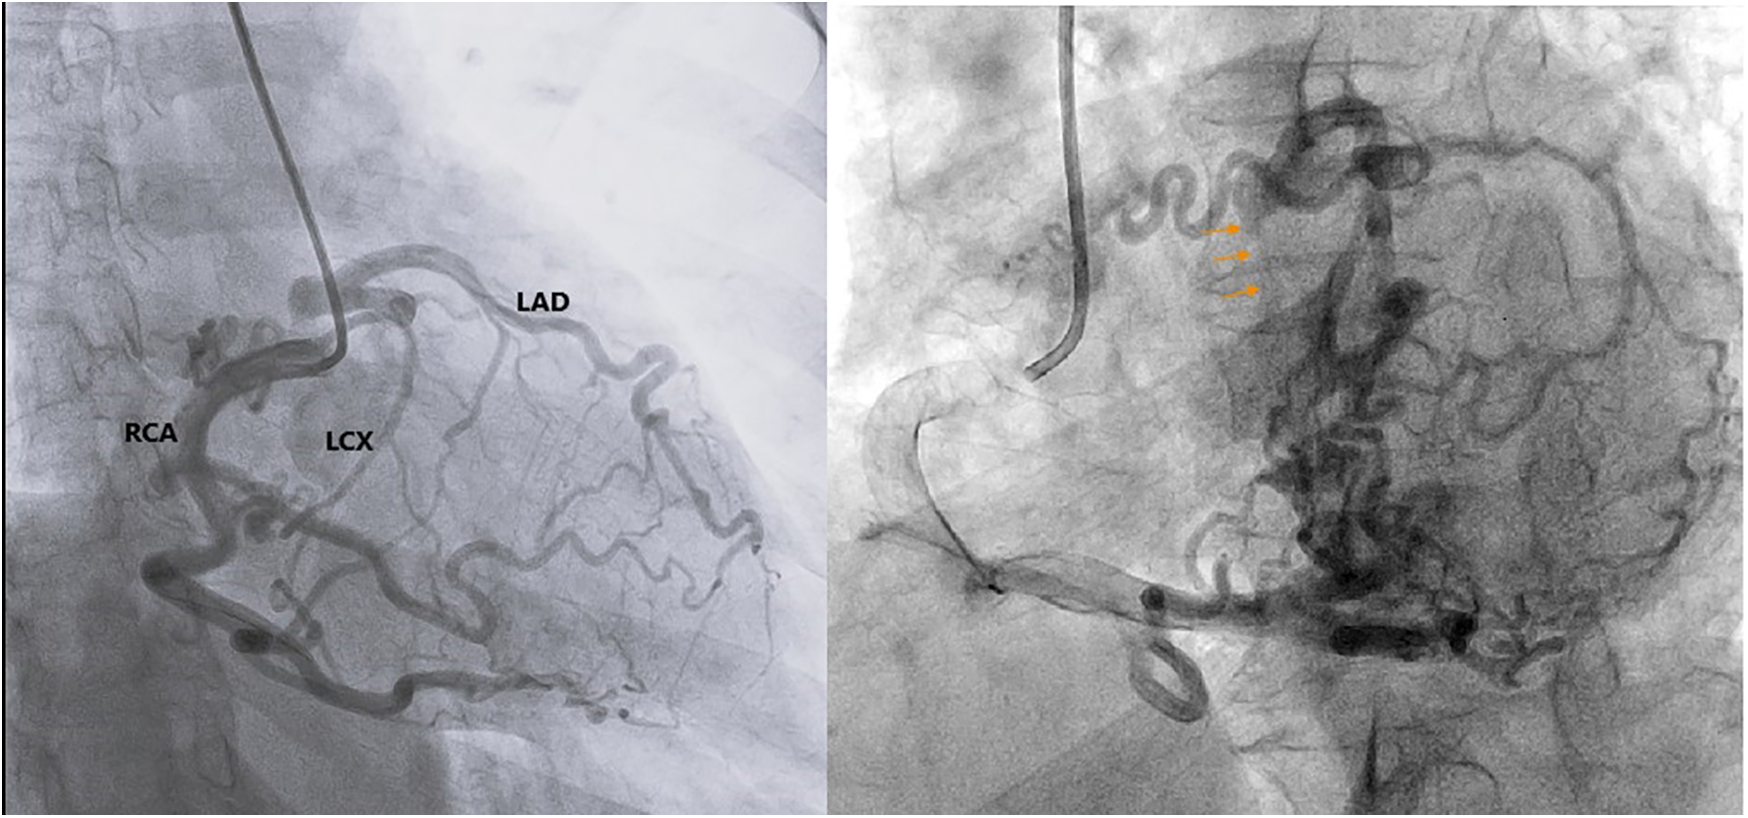

The patient subsequently underwent coronary angiography to confirm the diagnosis. Angiographic images revealed multiple tortuous collateral vessels originating from a dilated RCA, draining into the LAD, and subsequently into the LCx. The conus branch of the RCA, the acute marginal, posterior descending artery, and posterolateral branches were observed to contribute collateral flow into the LAD (Figures 1, 2). The LMCA was confirmed to originate below the aortic annular plane, evidenced by retrograde contrast flow from the LMCA into the LVOT (Figure 2, Supplementary Video S2). There were no other lesions identified in the LAD, LCx, or RCA arteries.

Figure 2. Coronary angiography confirms the LMCA originating below the aortic annular plane, evidenced by retrograde contrast flow from the LMCA into the LVOT (orange arrows). LAD, left anterior descending artery; LCX, left circumflex artery; RCA, right coronary artery.